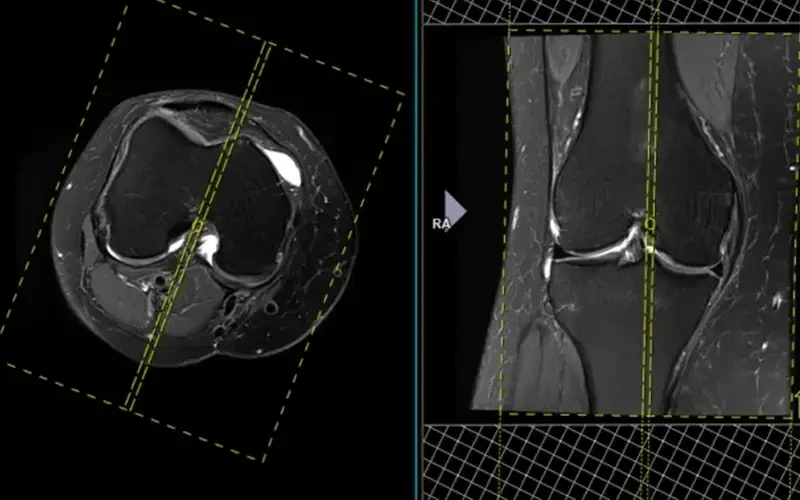

مقایسه MRI و آرتروسکوپی در تشخیص آسیب‌های منیسک یکی از موضوعات مهم در ارتوپدی زانو است. پارگی منیسک از شایع‌ترین آسیب‌های مفصل زانو محسوب می‌شود که تشخیص دقیق آن نقش تعیین‌کننده‌ای در انتخاب روش درمان دارد. MRI به عنوان روش تصویربرداری غیرتهاجمی با دقت بالا شناخته می‌شود، در حالی که آرتروسکوپی علاوه بر تشخیص، امکان درمان همزمان را فراهم می‌کند. در این مقاله به بررسی تفاوت‌ها، مزایا، محدودیت‌ها و کاربردهای هر دو روش می‌پردازیم تا بیماران و پزشکان بتوانند با آگاهی کامل درباره انتخاب بهترین مسیر تشخیصی تصمیم‌گیری کنند.

MRI روشی غیرتهاجمی با حساسیت و ویژگی بالا در تشخیص پارگی منیسک است. این روش می‌تواند محل، نوع و شدت آسیب را نشان دهد و همزمان وضعیت رباط‌ها و غضروف را نیز بررسی کند.

در مقایسه MRI و آرتروسکوپی در تشخیص آسیب‌های منیسک باید توجه داشت که آرتروسکوپی به عنوان استاندارد طلایی شناخته می‌شود، زیرا جراح به صورت مستقیم داخل مفصل را مشاهده می‌کند. با این حال، این روش تهاجمی بوده و نیاز به بیهوشی دارد.